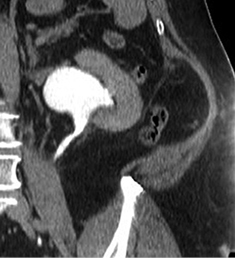

2019 m. gegužės 7 d. (praėjus apie 6 mėn. po operacijos) atlikta kompiuterinė tomografija (4 pav. B). Kairiojo inksto kolektorika kiek prasiplėtusi, geldelė iki ~42 mm pločio, kontrastinę medžiagą (k/m) skiria laiku, kontrastuojasi, k/m nuteka šlapimtakiu į šlapimo pūslę. Kairysis šlapimtakis neprasiplėtęs, proksimalinėje dalyje jo spindis iki 5,5 mm diametro, distalinėje dalyje – iki 7 mm. Ties šlapimtakio proksimaline dalimi matyti infiltruoti aplinkiniai audiniai (vertinama kaip pakitimai po buvusios operacijos). Kitų pakitimų šlapimo takuose nenustatyta.

2019 m. spalio 9 d. (praėjus apie 12 mėn. po operacijos), atlikus kompiuterinę tomografiją, matyti, kad kairiojo inksto geldelė mažiau išplėsta – iki ~26 mm pločio (buvo iki 42 mm), PUJ spindis – apie 2,5 mm pločio, distaliau šlapimtakis neišplėstas, jo spindis iki pat šlapimo pūslės išmatuojamas 3,5–5 mm, sienelės plonos, rentgenokontrastinių akmenų nematyti (4 pav. C). Ties PUJ periureteriniuose audiniuose – fibroziniai pakitimai, perinefriniuose audiniuose – dorzaliai riebalinio audinio ribotos pooperacinės sankaupos.

A

B

C

4 pav. Kompiuterinė tomografija (A – prieš operaciją; B – praėjus 6 mėn. po operacijos; C – praėjus 12 mėn. po operacijos)